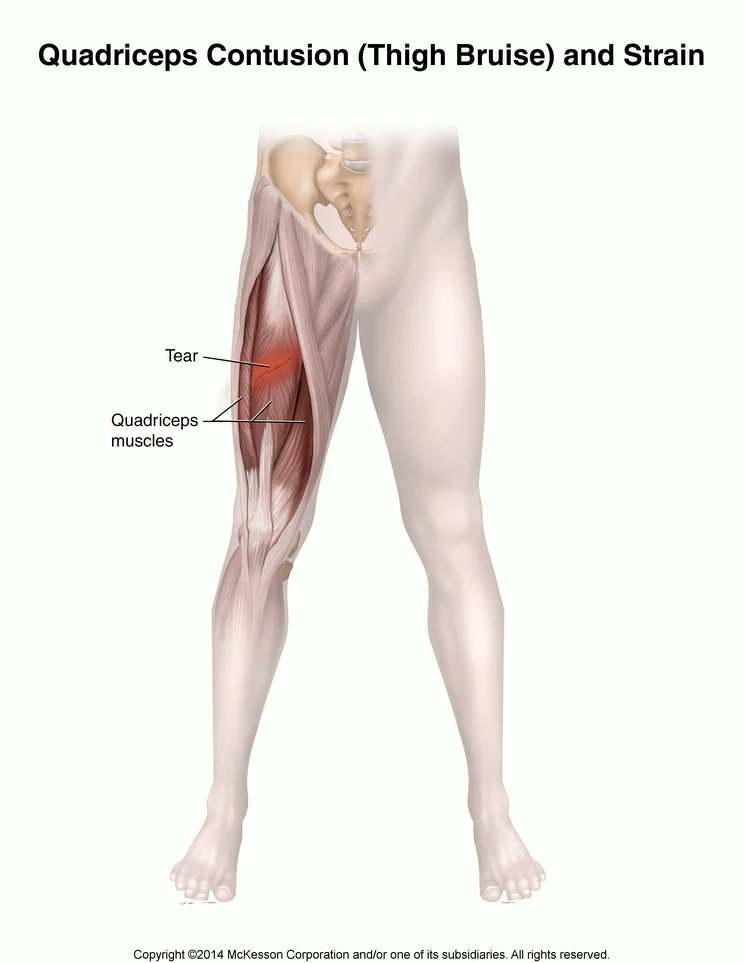

٩٢% من الاصابات العضلية في كرة القدم تحدث في مجموعة العضلات الكبرى السفلية:

٣٧% العضلات الخلفية

٢٣% العضلات الضامة

١٩% العضلات الامامية

١٣% عضلات الساق